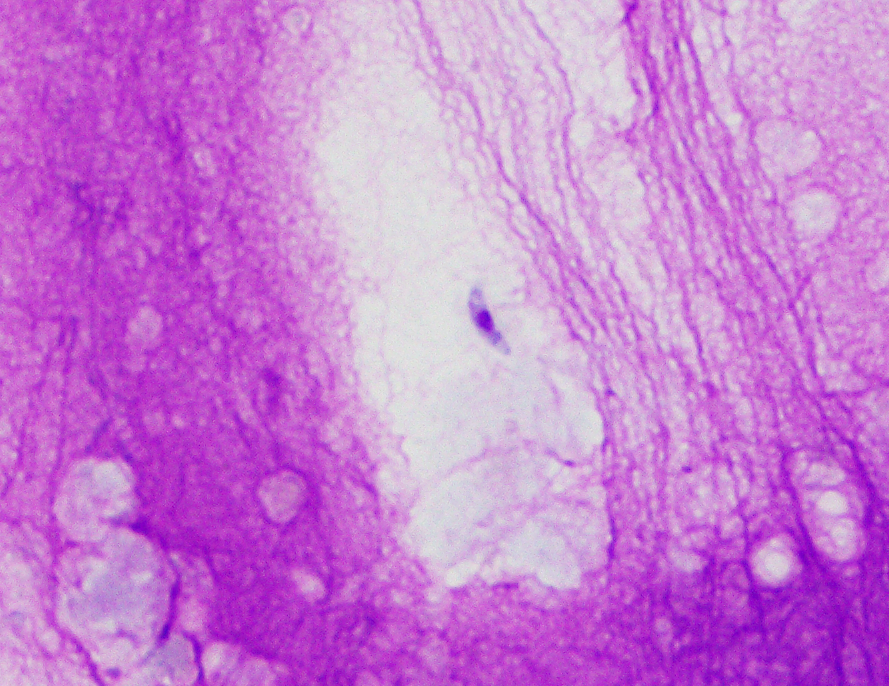

Cytology of liver:

Impressions: Inflammatory or infectious hepatopathy and probable cholangitis; cholangiohepatitis. During the abdominal ultrasound, fine needle aspiration of bile and biopsy of liver parenchyma is performed. Results are shown: